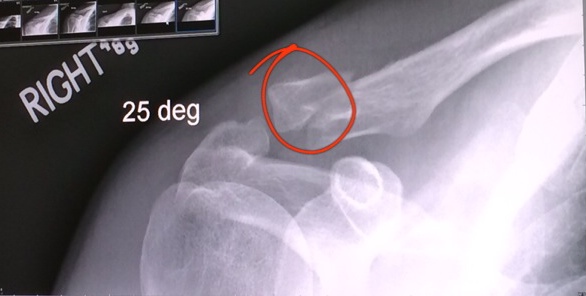

That shoulder pain was crazy!! I had broken a clavicle and barely felt it, why is he in so much pain??? I couldn’t figure it out. He got so sick of the pain that two days later we saw a sports orthopedist. Well, here’s the kick, he broke the clavicle in two places, so they whole shoulder was pretty much hanging. The bit broken in the middle was a bit lifted and so far that it would be quite hard for it to heal on its own, so the Dr. gave us the choice: wait 4-6 months and see how it heals, or do the surgery now and make sure it heals properly. If we waited and it didn’t heal properly, they’d have to go in, break the bone, fix it and wait for it to heal again. I told him it was his decision. He was all drugged up so we made the decision together to get the surgery. ASAP.

They told us to get there at 9:30 am, they took us in at 10:00 by 10:40 they put him in the stretcher, there was still someone ahead… I heard nothing until 1:30 pm, when the doctor came out with these pictures and made me a little drawing to explain how loose and up and twisted the little loose piece was. Surgery took two hours. He said it was quite probable not going to heal well if we didn’t have the surgery as the loose bit of bone was quite twisted and out of place. One more hour till he’d wake up.